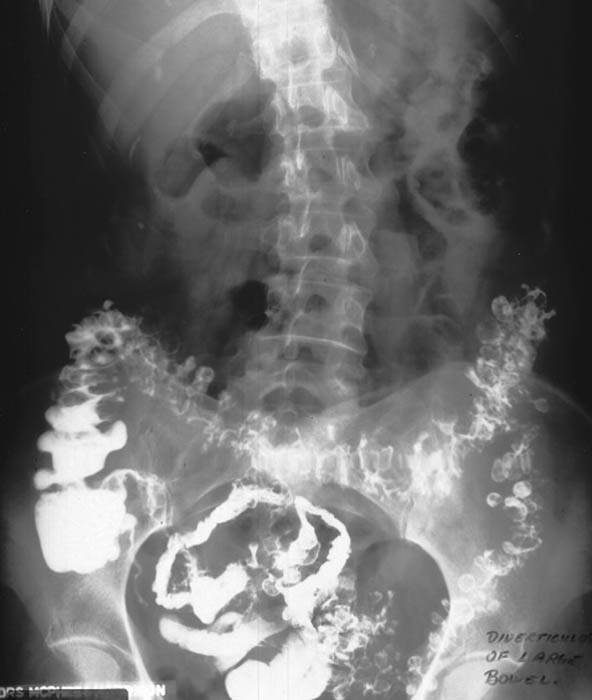

What are diverticula?

Outpouchings (herniations) of the mucosal layer through a weakened muscular layer of the bowel wall.

What is diverticulosis?

The presence of diverticula without inflammation.

Where do diverticula most commonly occur?

The sigmoid colon.

Do diverticula usually occur singly or in groups?

In groups, not singly.